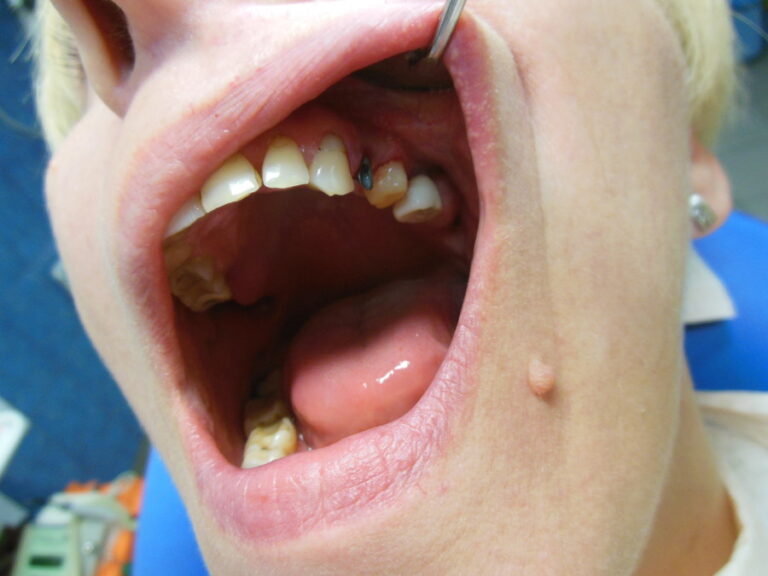

Przykłady zabiegów

Ortodoncja CBCT

Leczenie chirurgiczno-ortodontyczne wad zębowych z zastosowaniem tomografii spiralnej CBCT w naszej klinice.